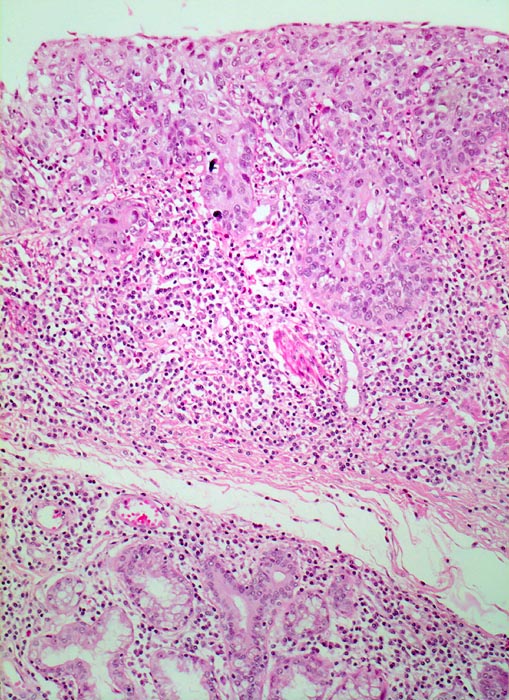

Carcinoma in situ der Ösophagusschleimhaut

Mukosa aus dem Randbereich des Karzinoms mit schwerer Dysplasie des Plattenepithels (Carcinoma in situ). Die Zellen sind unregelmässig angeordnet und zeigen anstelle der normalen Ausreifung auf der ganzen Epithelbreite deutlich vergrösserte hyperchromatische Kerne. Das Epithel bildet unregelmässige Zapfen, die in das Stroma vordringen. Die Basalmembran scheint in diesem Bildausschnitt jedoch erhalten. Die Submukosa enthält ein dichtes gemischtes Entzündungsinfiltrat. Am unteren Bildrand sind submuköse Schleimdrüsen erkennbar.

Jahrelanger Nikotin- und Ethylabusus. Vor 6 Monaten ergab die Abklärung wegen progredienter Dysphagie ein inoperables stenosierendes Karzinom im distalen Ösophagus. Der Patient verstirbt am Tumorleiden.